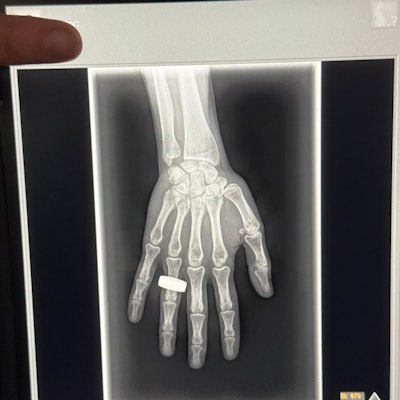

The commander of the Fram2 space mission has posted on social media what may be the first x-ray image taken in space.

In an April 1 post on the social media platform X, Chun Wang wrote that on the second morning of the flight, the crew woke up, had breakfast, and “took a few x-ray images.”

Image from an X post by @satofishi.

The post has received over 14.9 million views at the time of writing. The image appears to be a nod to the first x-ray ever taken by Wilhelm Roentgen of his wife Anna Bertha Ludwig's hand on December 22, 1895.

The Fram2 mission launched on March 31 and is expected to be in orbit for at least another day. The crew is conducting more than 20 science experiments, including taking images of each other with an ultraportable x-ray machine.